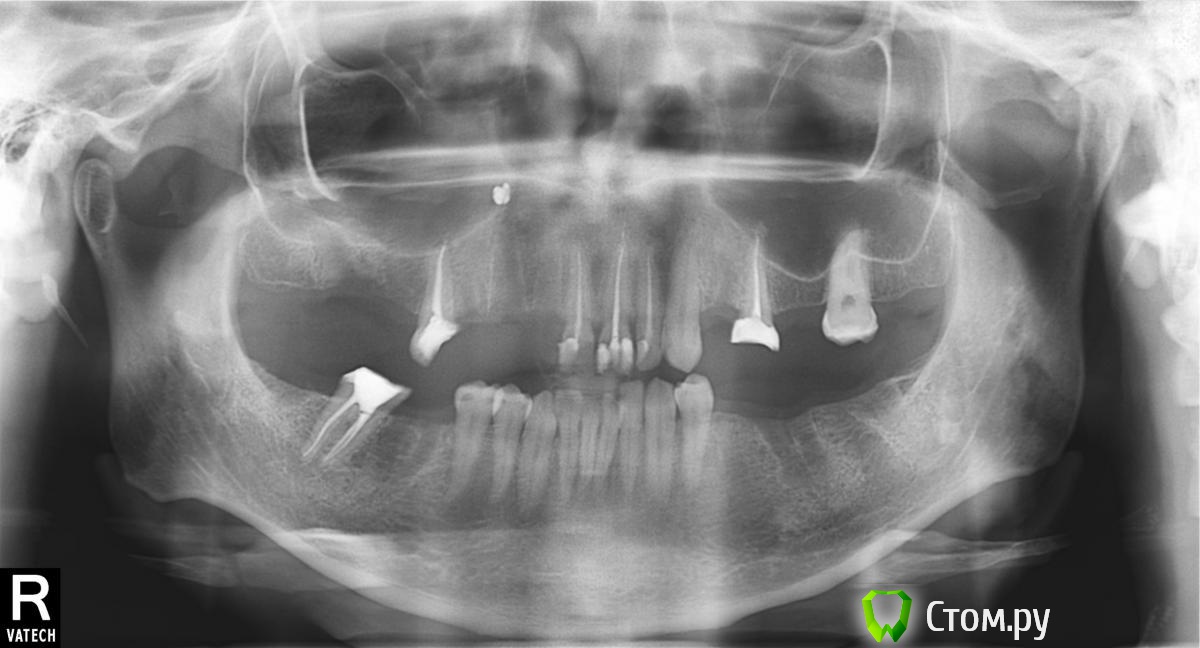

Portnoi Опубликовано 12 мая, 2014 Поделиться Опубликовано 12 мая, 2014 Добрый вечер. Решил заняться своими зубами. как я их довел до такого состояния отдельный разговор. ищу варианты дальнейшего лечения. был предложен вариант имплантации 11 зубов. дорого, но не из-за того что я жадный. а из-за жизненной ситуации, деньги могут понадобится на лечение родственника. только в 3й по счету клиники предложили поставить мостовидные протезы слева вверху (в сумме 5 зубов) и справа снизу (в сумме 3 зуба). сей час меня интересует вопрос, можно ли имплантировать не все зубы? все имплантологи хотят что бы у меня было 28 зубов. можно ограничиться только теми, что недавно были удалены? просто 3х зубов у меня лет 10 нет, а живать я привык остатками корней=) если честно мне и сей час не плохо, но эстетики не хватает. сьемные протезы ставить не хочу. но если вариант лечения не подберу, то придется… панорамный снимок имеется. кт еще не делал. рано.спасибо! Ссылка на комментарий

sydnik Опубликовано 12 мая, 2014 Поделиться Опубликовано 12 мая, 2014 здравствуйте! на мой взгляд относительно бюджетный вариант таков: право верх имплатация в обл 6 зуба(возможно потребуется операция по поднятию синуса, нужно сделать кт и консульт хирурга), дальше по снимку у вас осталась 5 - ка и нету 3 зубов( корень в обл 4 тяжело сказать что делать- размыто на снимке, варианты такие штифт в корень или имплант и того еще 3 импланта. перед группу одиночные коронки кроме клыка. лево верх имплант в обл отсуствую 4 и мост 5-7( а лучше имплант в обл 6 зуба)лево низ либо 3импланта [ 5 67]либо 2 импланта. 57- мостправо мост 7-5 либо имплан в обл 6это по вашему рентгену, возможно, при очной консультации может что- то поменятся но не намного надеюсь все понятно написал 1 Ссылка на комментарий

sydnik Опубликовано 12 мая, 2014 Поделиться Опубликовано 12 мая, 2014 по этому снимку тяжело говорить о кистах на зубах, по крайней мере чего - то страшного я не вижу.надо сделать кт и посмотретьсьемные протезы уничтожат кость и потом качественное протезирование будет стоить еще больше, я бы не рекомендовал их, только как временный вариант после имплантации. и кстати, в этот момент( ношение сьемных) вы бы убедились как с ними " хорошо":) 1 Ссылка на комментарий

Bier Опубликовано 12 мая, 2014 Поделиться Опубликовано 12 мая, 2014 КТ делать делать через пару мес вместе с рентгенконтрастным хирургическим шаблоном во рту.Делать передние зубы без боковых нельзя. Хватило бы 9 имплантатов и синуслифт слева. 1 Ссылка на комментарий